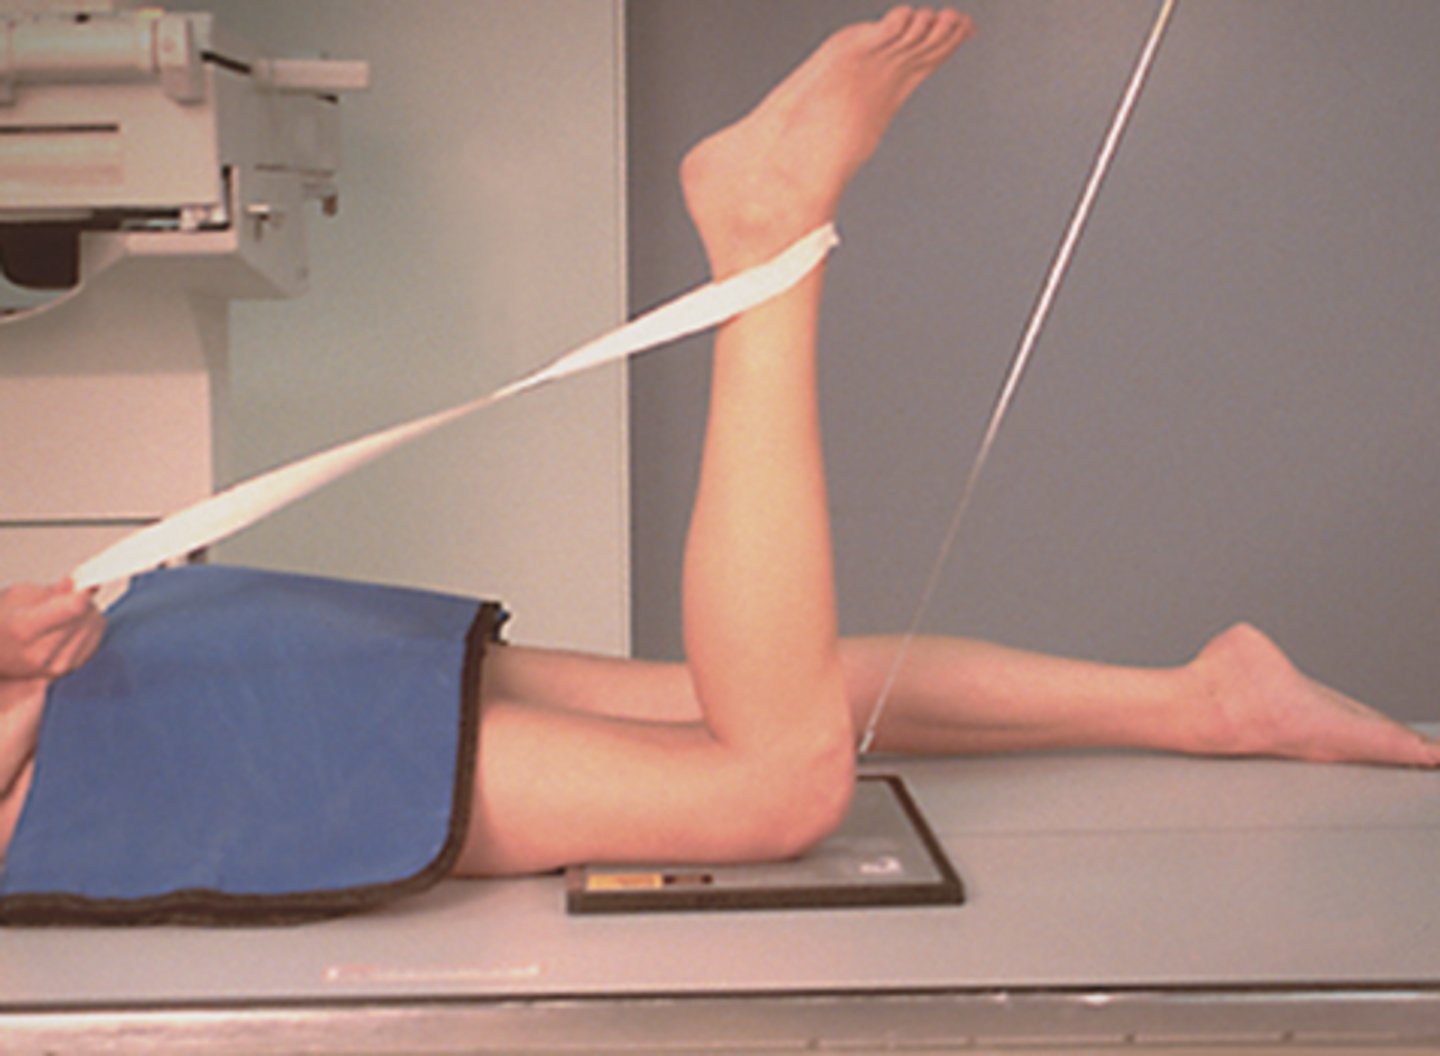

In which cases would you need to do a HBL projection of the KNEE?

- for TRAUMA patients; usually patients presented supine on a trolley.

- used to check for FRACTURES of the knee joint OR ruptured quadriceps tendon.

- may also be used to check for lipohaemarthrosis

When doing a HBL projection of the knee for trauma patients, why should the leg NOT be flexed at all?

- it could cause further damage in the knee joint & worsen the pain.